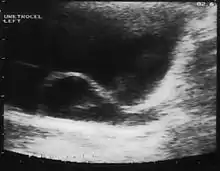

Ureterocele

A ureterocele is a congenital abnormality found in the ureter. In this condition the distal ureter balloons at its opening into the bladder, forming a sac-like pouch. It is most often associated with a duplicated collection system, where two ureters drain their respective kidney instead of one. Simple ureterocele, where the condition involves only a single ureter, represents only twenty percent of cases.

Since the advent of the ultrasound, most ureteroceles are diagnosed prenatally. The pediatric and adult conditions are often found incidentally, i.e. through diagnostic imaging performed for unrelated reasons.